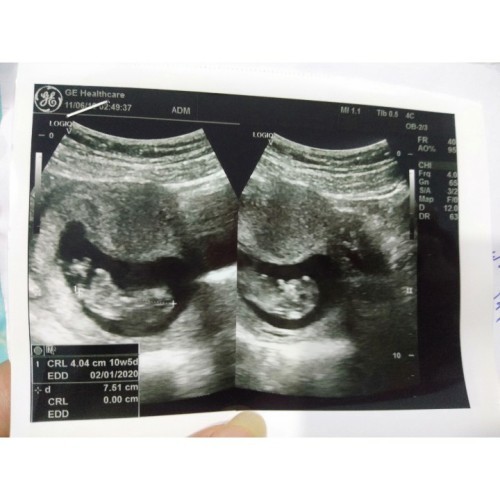

ตอน10 W 5 D ค่ะ